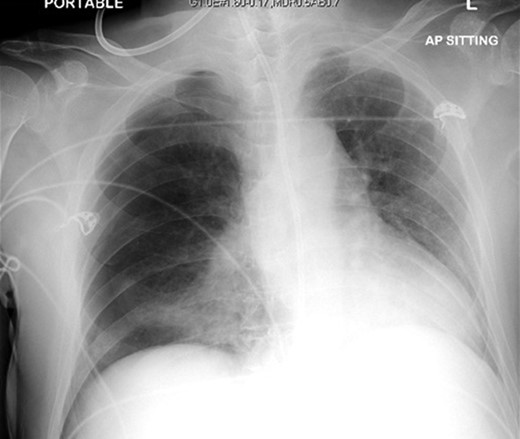

A 72-year-old male was admitted to a tertiary hospital following a cerebrovascular accident. His neurological deficits were global aphasia, dysphagia and right hemiplegia. He underwent a routine NGT change with a small bore NGT by an experienced nurse on Day 2 of admission. The nurse was unable to obtain any aspiration from the newly inserted NGT and a chest radiograph was done to confirm placement as per hospital protocol. This showed a malpositioned NGT, traversing the right main bronchus with the tip of tube in the right costophrenic sulcus (Fig. 1). She was alerted about the chest radiograph findings and removed the tube before reinserting another NGT. The subsequent aspiration from the NGT had a pH of 7, hence another chest radiograph was done which now demonstrated a right pneumothorax (Fig. 2). The pneumothorax was likely due to intrapulmonary placement of the earlier NGT.

Chest X-ray following removal of the nasogastric tube, with interval development of a right sided pneumothorax.